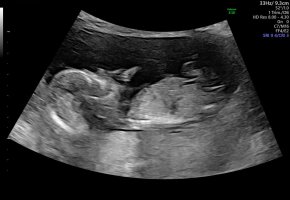

Jeg bestilte en privat ultraltd dagen etter otul da de ikke var i posisjon til å se nub og de ikke hadde tid igjen til å sjekke når jeg spurteÅååå, tusen takk, så spennende! Tror ikke vi klarer å vente til ordinær ultralyd før vi får vite, så mulig det må bli en privat tidlig ultralyd om et par uker. Gøy å høre hva du tenker![]()

Jeg hadde tenkt at jeg klarte å se det selvom de ikke sa noe, men det kom aldri i det perspektivet.